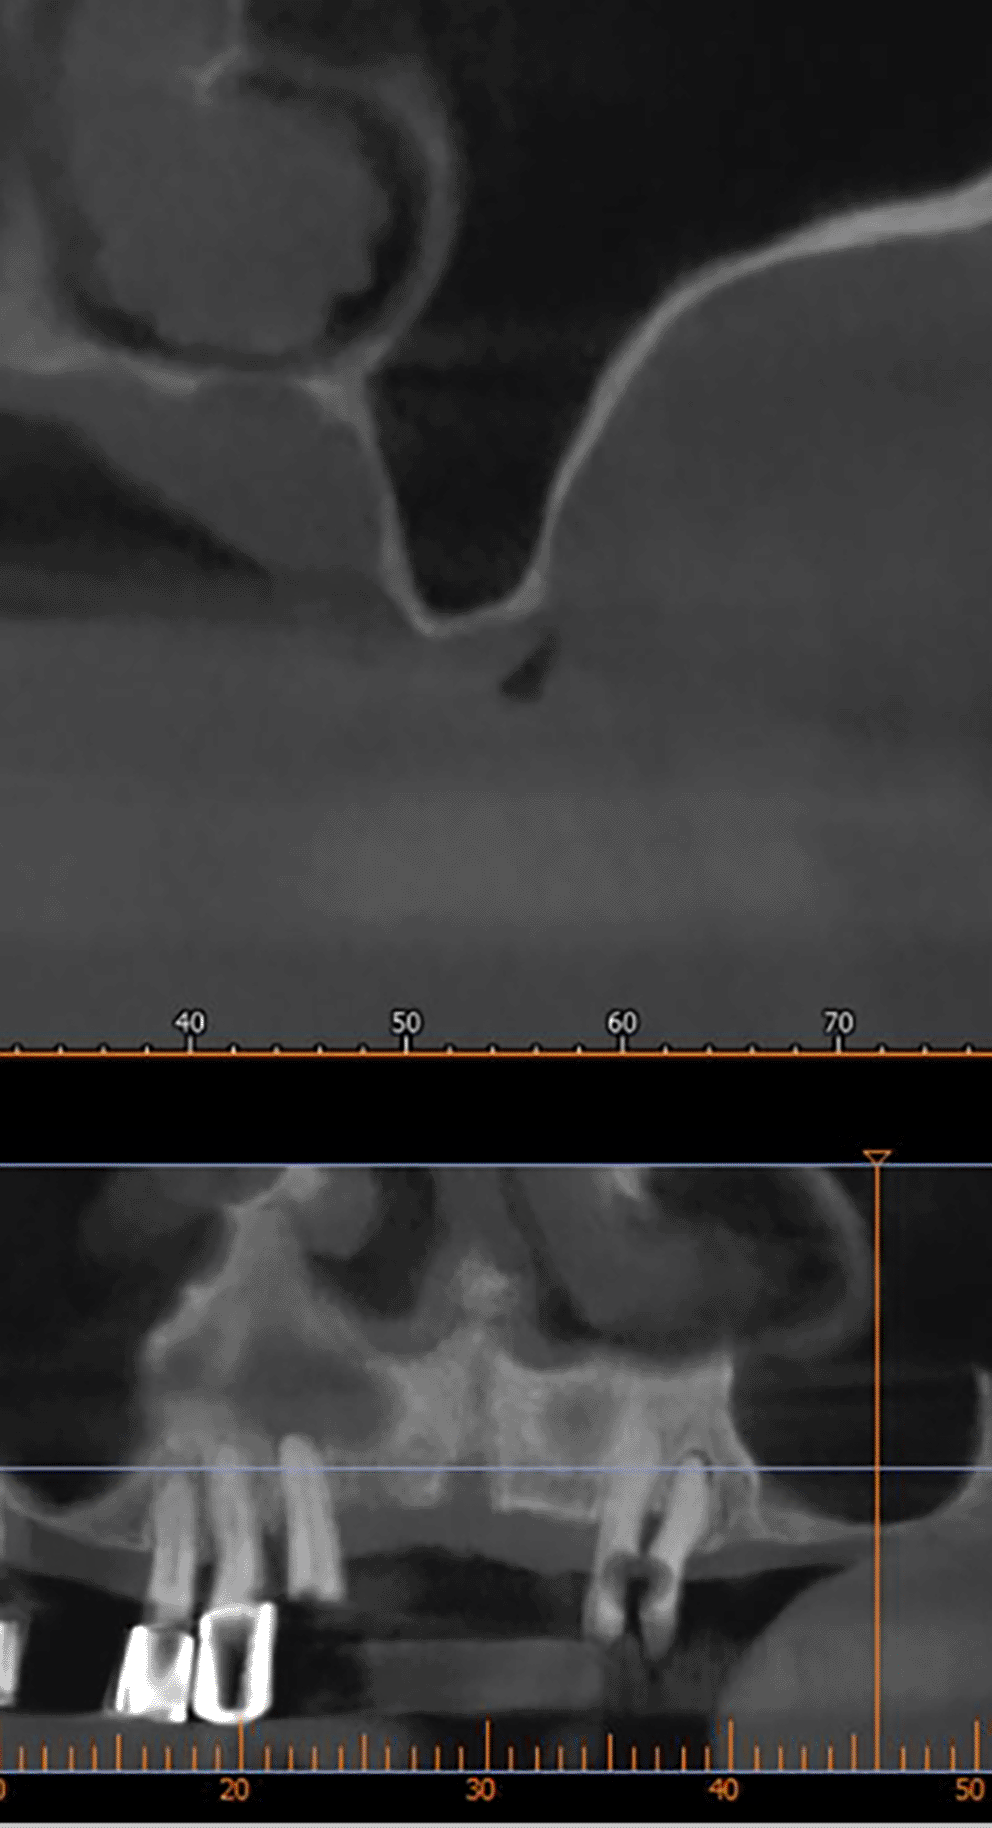

A CBCT scan was performed immediately after grafting and showed a direct bone gain of (11.4 mm) ( Figure 10) and 9 months after bone grafting where subsequent bone gain (11.4 mm) was found ( Figure 11).

3928750d-b091-43c3-94bb-6b181f3845d3_figure11.gif

Figure 11. CBCT 9 months after grafting.